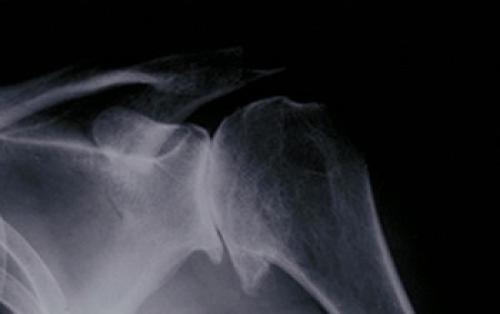

Обхват плеча или выскакивание – очень распространенная жалоба. Еще более распространено ощущение хруста в плече. Плечо – очень сложное соединение, поэтому есть много структур, которые могут щелкнуть, издать звук или хруст, когда они ранены или воспламенились. Плечо содержит мускулы, кости, сухожилия, хрящ и бурсу.

Лопатка – это плоская широкая кость, которая расположена свободно в толще мышц по задней поверхности грудной клетки. Между лопаткой и грудной клеткой находятся синовиальные сумки для уменьшения трения при движениях. Если при движениях возникают щелкающие звуки, хруст и прочие звуковые феномены, врачи говорят о синдроме «щелкающей лопатки».

Плечевой сустав состоит из плечевой кости, сустава, которые соединены с ключичным суставом. Головка плечевой кости примыкает к лопатке. Практически полное отсутствие нервных волокон в этой области, делает плечевой сустав одним из самых подвижных, но, и хрупких.

Верхняя часть плечевой кости, с помощью которой происходит соединение, имеет шарообразную форму, а составная впадина лопатки, которая соединяется с плечевой костью, представляет собой маленькую впадину. Эта «ямка» смягчает уровень трения плечевой кости при движении.